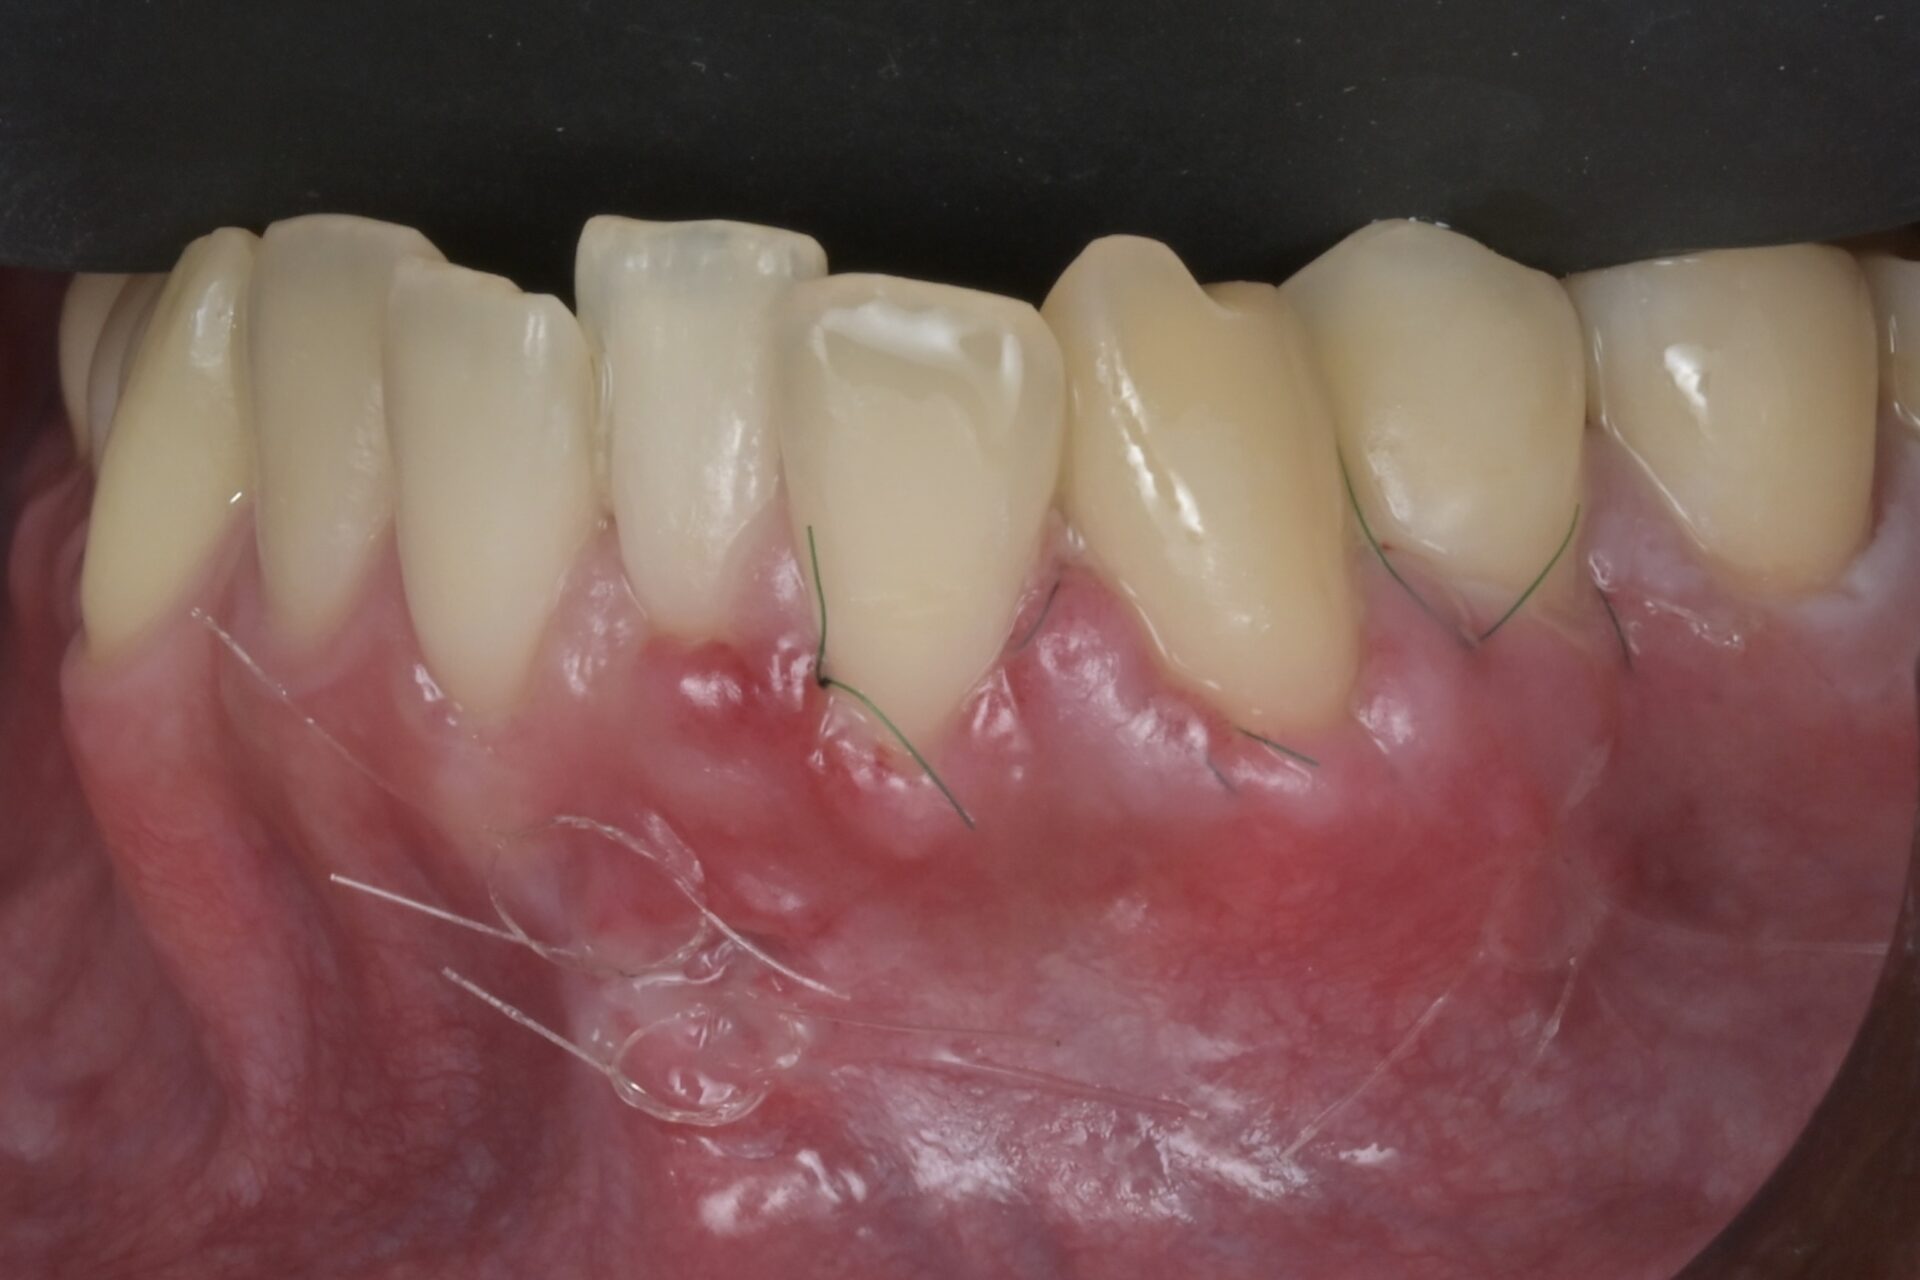

術後3週間

抜糸しました。治癒は良好です -

術後4週間

根面被覆が達成されています。